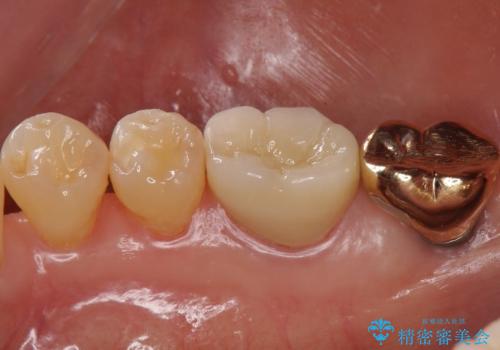

不適合だった詰め物の裏側に大きな虫歯がありました。

セラミックインレーやアンレーでは強度に不安が残るため、クラウンでの修復処置としました。

クラウンでは歯のがたつきを修正することもできます。

虫歯の除去と歯の捻転の両方を解決することができました。